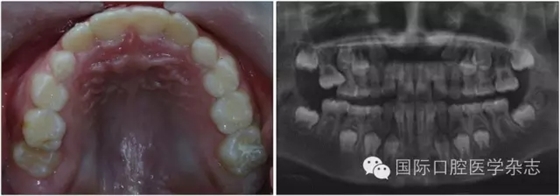

牙齒異位萌出是指恒牙在萌出過(guò)程中,未在牙列的正常位置萌出,兒童口腔臨床最常見的是上頜第一恒磨牙和上頜尖牙的異位萌出。造成第一恒磨牙異位萌出的原因包括:第二乳磨牙和第一恒磨牙的牙冠體積較大;頜骨的發(fā)育不足,尤其是上頜結(jié)節(jié)發(fā)育不足;第一恒磨牙的萌出角度異常,牙軸向近中傾斜等,歸根結(jié)底是在第一恒磨牙萌出階段出現(xiàn)了牙量和骨量不調(diào)的問(wèn)題,頜骨發(fā)育不足是最主要的原因。發(fā)生率為2%~6%,男性多于女性,其中2/3發(fā)生在上頜,可單側(cè)或雙側(cè)對(duì)稱出現(xiàn)。第一恒磨牙的異位萌出常常造成第二乳磨牙早失,牙弓長(zhǎng)度減小。臨床上,常用分牙簧分離第一恒磨牙與第二乳磨牙,或使用恒磨牙面粘著舌扣的Halterman矯治器,或變異Nance弓推第一恒磨牙向遠(yuǎn)中的方法,改變恒牙萌出道,阻斷恒磨牙對(duì)乳磨牙的壓迫吸收,引導(dǎo)恒磨牙正常萌出。圖7顯示為一左上第一恒磨牙異位萌出的患兒,左上第二乳磨牙松動(dòng),牙弓長(zhǎng)度減少[6]。

左:口內(nèi)照;右:全景片。

圖7 左上第一恒磨牙異位萌出,左上第二乳磨牙松動(dòng)

Fig 7 Ectopic eruption ofleft upper the first permanent molar, loose of left upper the second primarymolar